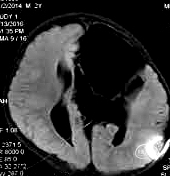

22个月后,内镜下造瘘术,泵压力逐步调高

造瘘术后3个月